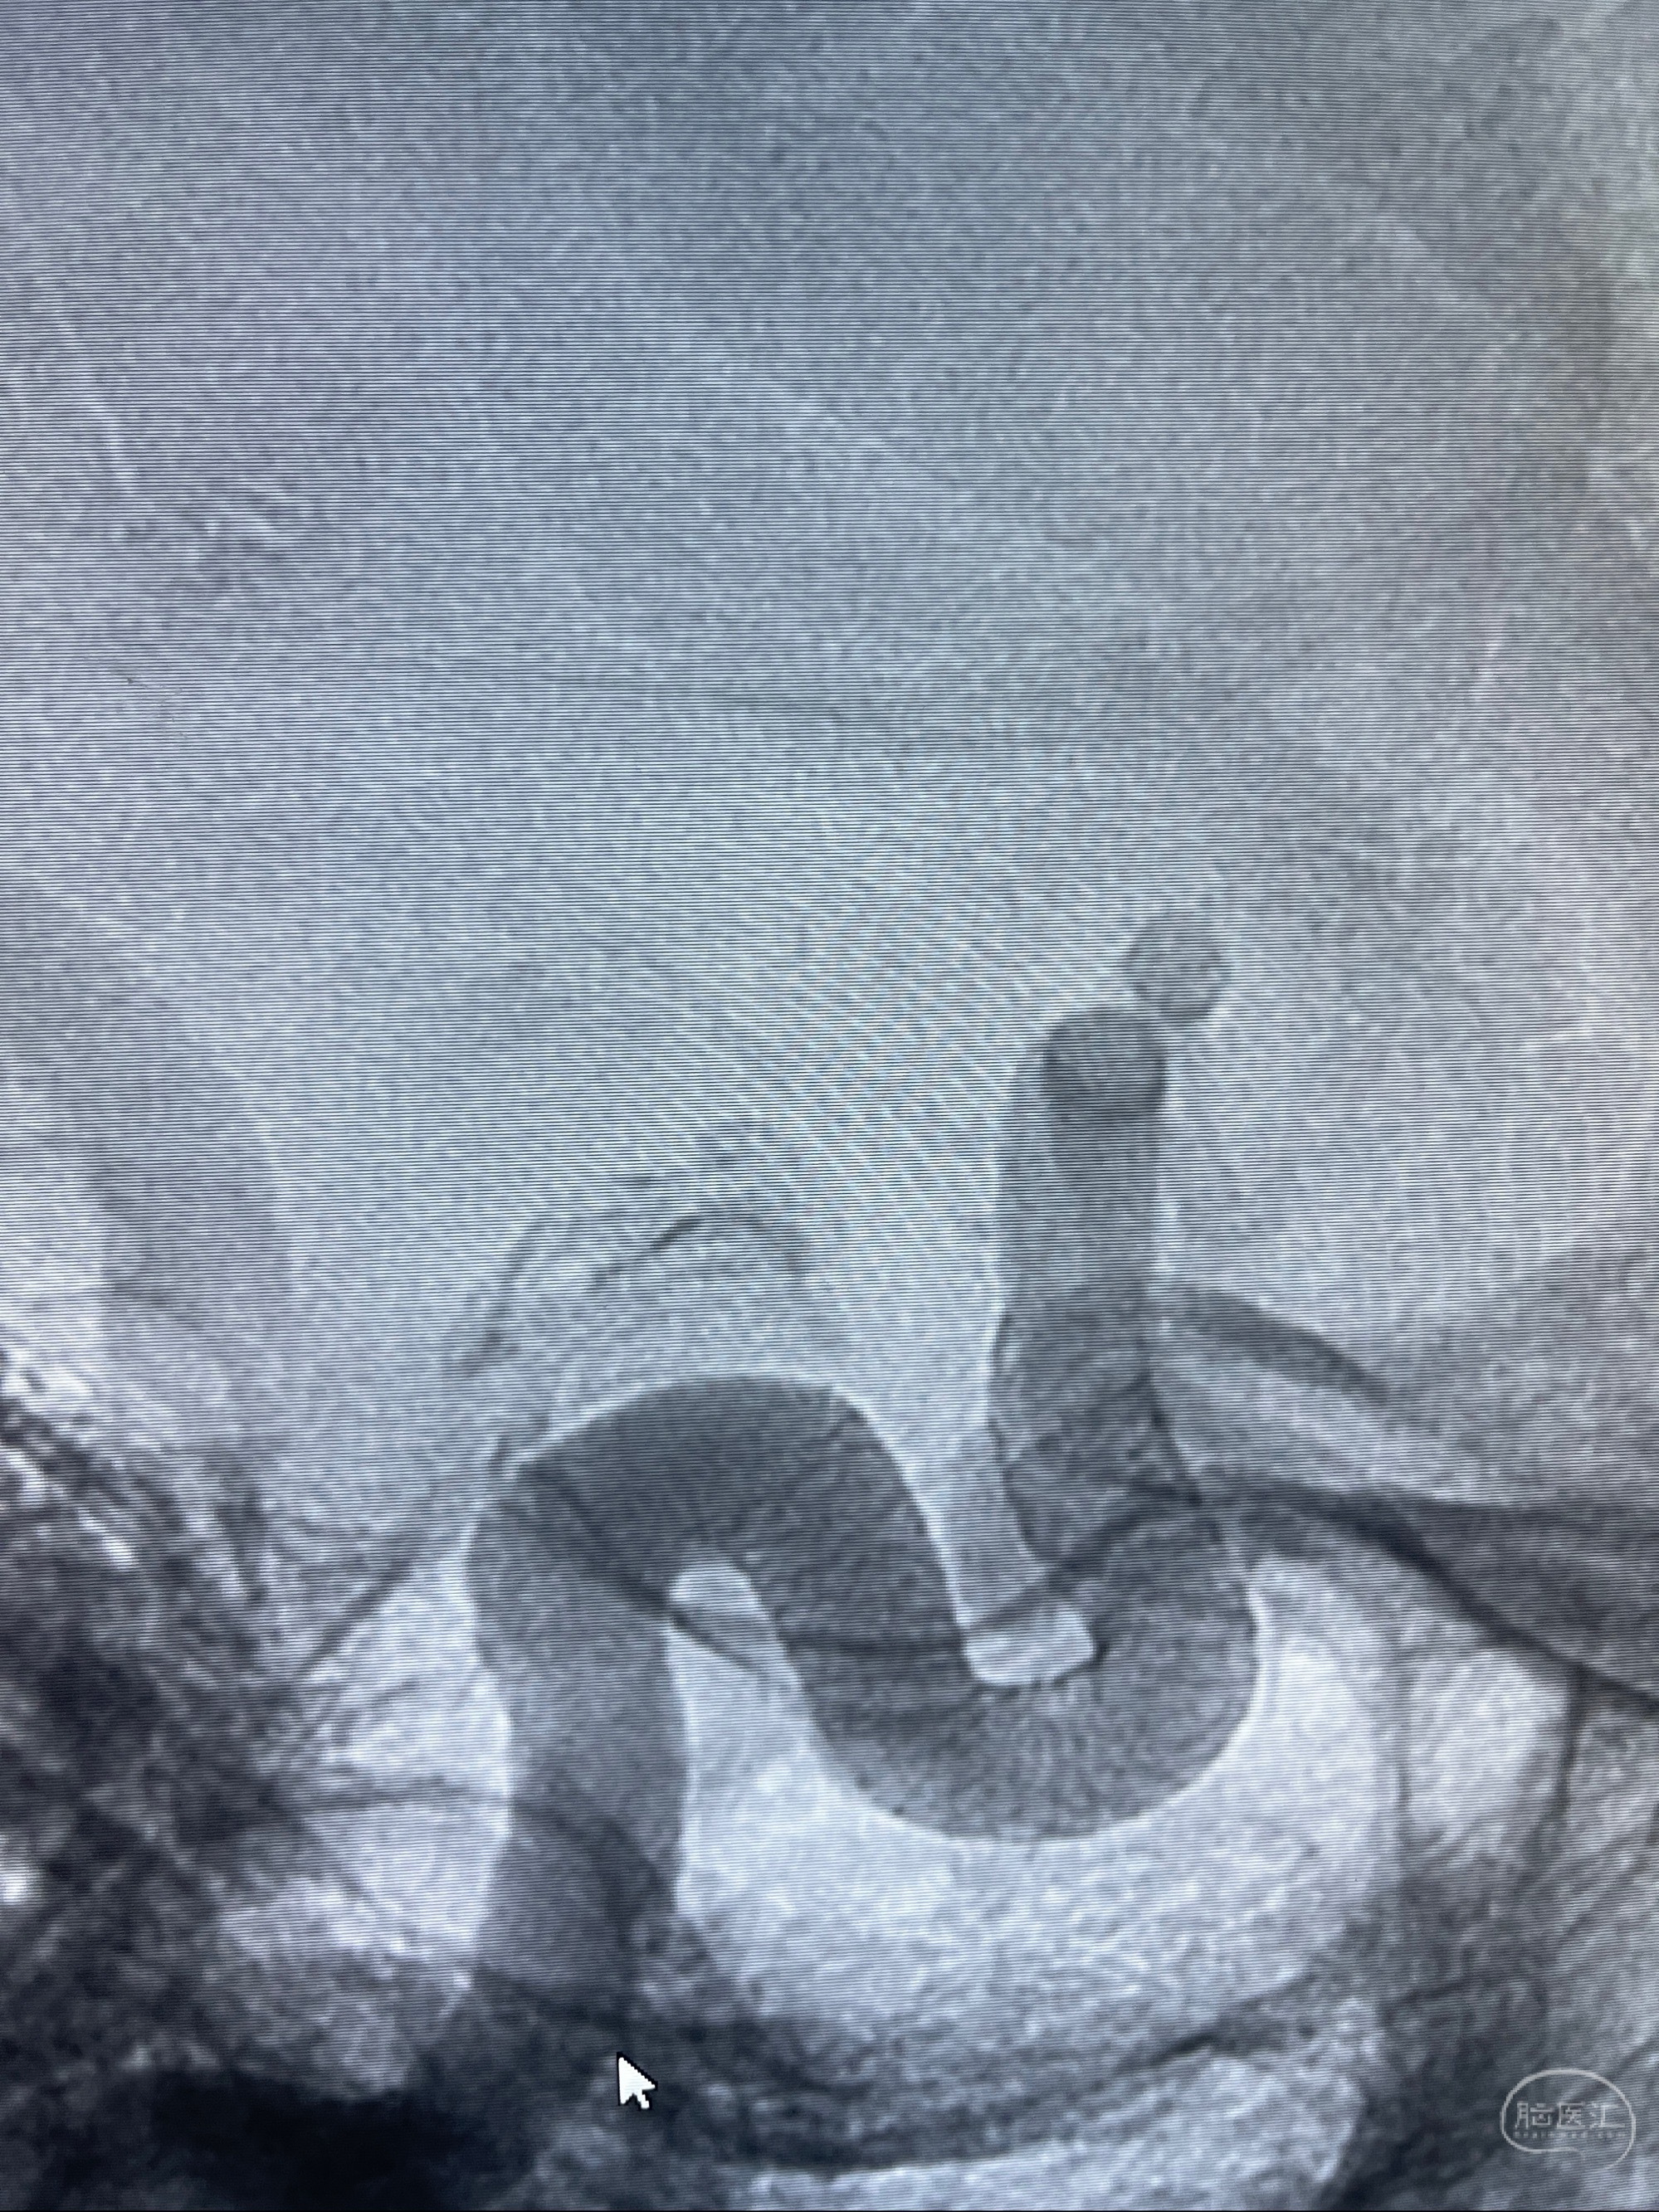

2023.07.25 泰州市人民医院查头颅CTA提示右侧C6段瘤样突起,建议DSA检查;

CTA示:右侧颈内动脉C6段见指向下方的突起,余左侧颈内动脉、双侧椎动脉、大脑前动脉、大脑中动脉、大脑后动脉及基底动脉走形正常,未见明显扩张及狭窄,局部未见明显瘤样扩张。

2023-07-27全脑血管造影:双侧颈内动脉眼动脉段动脉瘤,右侧较大